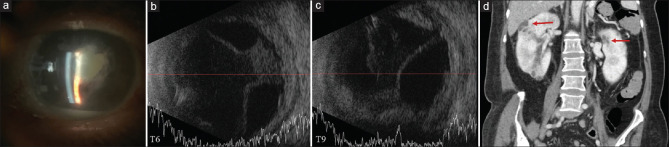

肺炎克雷伯菌(肺炎克雷伯菌)是东亚地区内源性眼内炎的常见病因,但在美国仍是一种不常见的内源性眼内炎病因。最近的报道已经描述了高毒力肺炎克雷伯菌菌株的出现,现在认为这是内源性肺炎克雷伯菌眼内炎的主要原因。我们记录了从2022年到2024年在洛杉矶县发生的4例内源性克雷伯氏菌眼内炎病例,其中2例确诊继发于高毒力菌株。前两例发生于女性糖尿病患者并发肾脓肿。虽然两名患者最初都接受了全身和玻璃体内抗生素治疗,但他们最终都需要剜出或去核。第三例发生在一名54岁的糖尿病男性,他表现为左眼全眼炎,随后发现有多发肝脓肿。我们的最后一个病例发生在一位47岁的男性糖尿病患者,伴有双侧内源性眼内炎和弥散性脑、肺和肝脓肿,符合肺炎克雷伯菌侵袭综合征。后两例患者均接受玻璃体内及全身抗生素治疗,并行玻璃体切除术。这些病例强调了认识内源性克雷伯氏菌眼内炎作为糖尿病患者潜在并发症的重要性,以及它与肝和肾脓肿的关系,因为及时的系统检查可能有助于及时诊断和干预。

Klebsiella pneumoniae (K. pneumoniae) represents a frequent cause of endogenous endophthalmitis in East Asia but remains an uncommon cause of endogenous endophthalmitis in the United States. Recent reports have characterized the emergence of hypervirulent K. pneumoniae strains, which are now thought to be the predominant cause of endogenous K. pneumoniae endophthalmitis. We document four cases of endogenous Klebsiella endophthalmitis in Los Angeles County from 2022 to 2024, including two cases confirmed secondary to a hypervirulent strain. The first two cases occurred in diabetic females with associated renal abscesses. While both patients were initially treated with systemic and intravitreal antibiotics, they ultimately required evisceration or enucleation. The third case occurred in a 54-year-old diabetic male, who presented with panophthalmitis of the left eye, subsequently found to have multiple hepatic abscesses. Our final case occurred in a 47-year-old diabetic male with bilateral endogenous endophthalmitis and disseminated cerebral, pulmonary, and hepatic abscesses consistent with K. pneumoniae invasive syndrome. Both the latter two patients were treated with intravitreal and systemic antibiotics, followed by vitrectomy. These cases underscore the importance of recognizing endogenous Klebsiella endophthalmitis as a potential complication in diabetic patients and its association with both hepatic and renal abscesses, as prompt systemic workup may facilitate timely diagnosis and intervention.